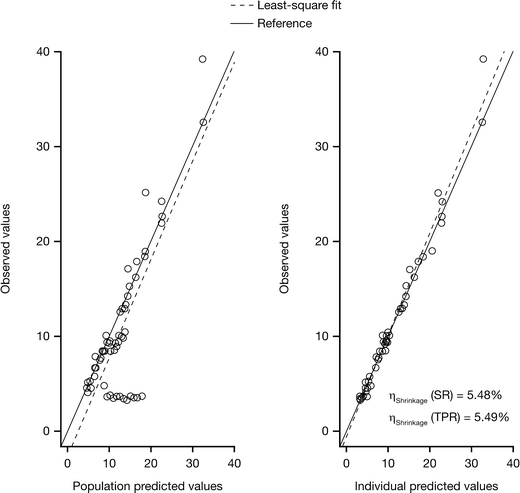

The model of tumor growth with the parameters for shrinkage and progression rates fitted the data for tumor size fairly well (Fig. 3). The observations versus population and individual predictions were uniformly and closely distributed around the line of identity. Table 5 lists the parameter and precision estimates. The covariate analysis identified that the shrinkage rate was significantly affected by EGFR mutation status. Figure 4 shows the individual model parameter estimates plots versus gender, ECOG status, dose level, and EGFR mutation status for the base model (without any covariates) and final model (EGFR on shrinkage rate). Shrinkage rate was 85% less in EGFR wild type versus EGFR mutant subjects. For the 15 mg cohort, although the variability around individual SR and TPR parameters was larger than for the other two dose groups, the available data did not support the addition of dose cohort as covariate, probably due to the small sample size evaluated in this study. No correlation with duration of treatment, progression-free survival, or overall survival was undertaken at this time.

Fig. 3

Observed tumor size versus population and individual predictions